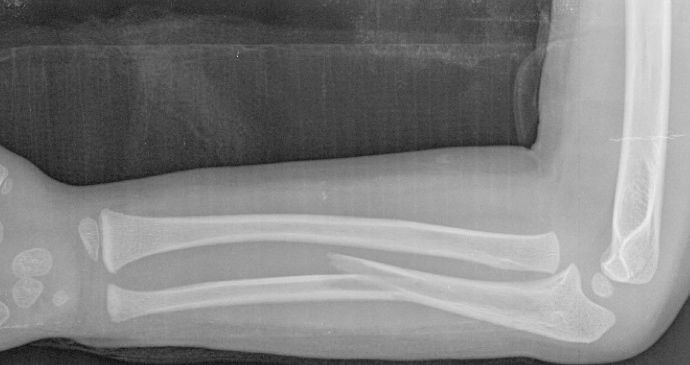

Las fracturas de ambos huesos del antebrazo al mismo nivel, con líneas de fractura oblicua-transversa o desplazamiento convergente son inestables y precisarán de tratamiento quirúrgico. En estos casos está indicado, dependiendo de la edad del paciente, el tratamiento mediante reducción y osteosíntesis. El enclavado intramedular elástico es el tratamiento de elección (Figura 15).

Figura 15: a-Imagen clínica de fractura de antebrazo derecho con gran deformidad. b- Radiografía donde se aprecia fractura de radio-cúbito de trazo transverso en el mismo nivel. c, d-Enclavado intramedular elástico. e,f- Imagen final con buena consolidación ósea.